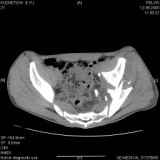

Уважаемые коллеги! Хотелось бы услышать совет по тактике лечения представлленого больного.Поступил после лечения в одном изотделений области. Травма 2,5 месяца назад. После выведенияиз шока был произведен остеосинтез перелома бедра, предплечья, до перевода к нам проводилосьвытяжение по оси шейки бедра за стержень, введенный в большой вертел. На сегодня деформацияригидна, клинически мобильности не определяется. Заранее признателен. P.S. Данный вид травм не включен в перечень "высокотехнологичных операций", направить длялечения по квотам Минздрава очень сложно.

Это обзорные и косые снимки

Привет, Леонид. Оскольчатый высокий двухколонный перелом в такие сроки трогать не надо, т.к. это про такие переломы сказано: "кто с ножом на Ж. пойдет тот в ней и останется...".